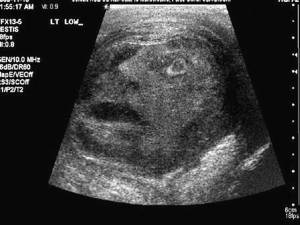

This x-ray of testicles taken at an Ontario University revealed something odd. It appears there's a terrorized man inside. Humble and Fred have similar pictures.